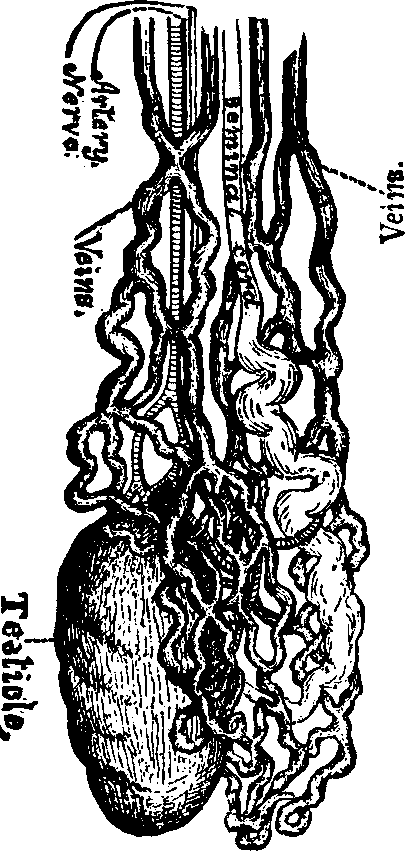

The function of the ovaries is to furnish ova or germs, and the functions of the uterus or womb are to secrete mucus; to exude the menses; to secrete the decidua; to contain and nourish the foetus and to effect its expulsion.

Flexions and Versions of the Womb. Flexion of the uterus, in which it is bent upon itself, as illustrated in Fig. 10, produces a bending of the cervical canal, constricting or obliterating it, and thus preventing the passage of spermatozoa through it. Version of the uterus [pg 710]in which its top, or fundus, falls either forward against the bladder (anteversion), as illustrated in Fig. 11, or backward against the rectum (retroversion), may close the mouth of the uterus by firmly pressing it against the wall of the vaginal canal, and thus prevent the passage of spermatozoa into the womb. 'The treatment of these several displacements will be considered hereafter. We may here remark, however, that they can be remedied by proper treatment. Our mechanical movements, manipulations, and kneadings are invaluable aids in correcting these displacements.